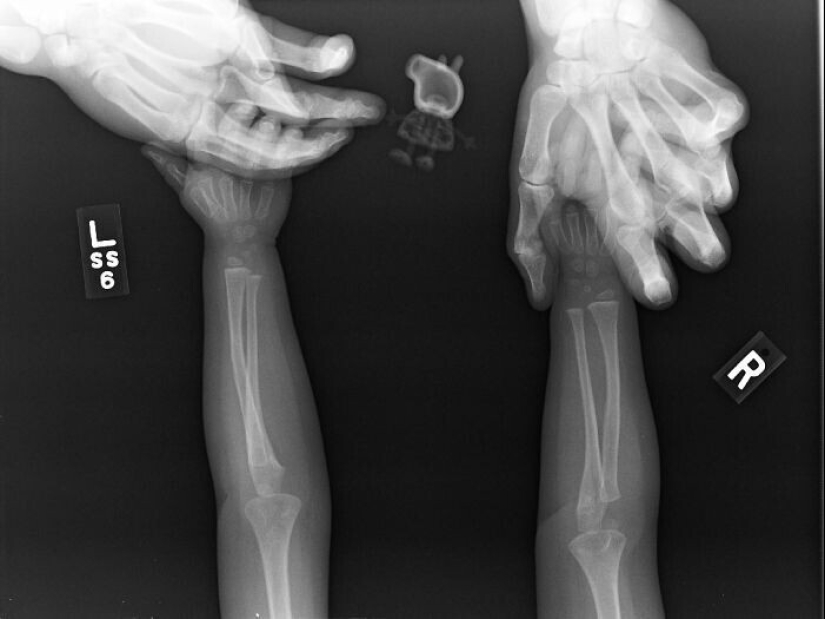

La artritis reumatoide